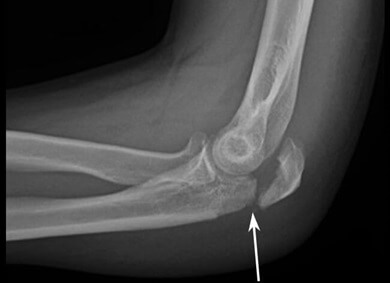

A lump on the elbow that appears suddenly and is associated with some kind of trauma e.g. fall, RTA or sporting tackle may indicate a bone fracture or joint dislocation.

There is typically immediate pain and swelling at the time of injury and it may be difficult to move your elbow.

Elbow fractures and dislocations are often accompanied by an obvious deformity around the elbow and there may be a hard lump if part of the bone has been forced out of place.

If you suspect your elbow lump is due to a fracture or dislocation, seek urgent medical attention.